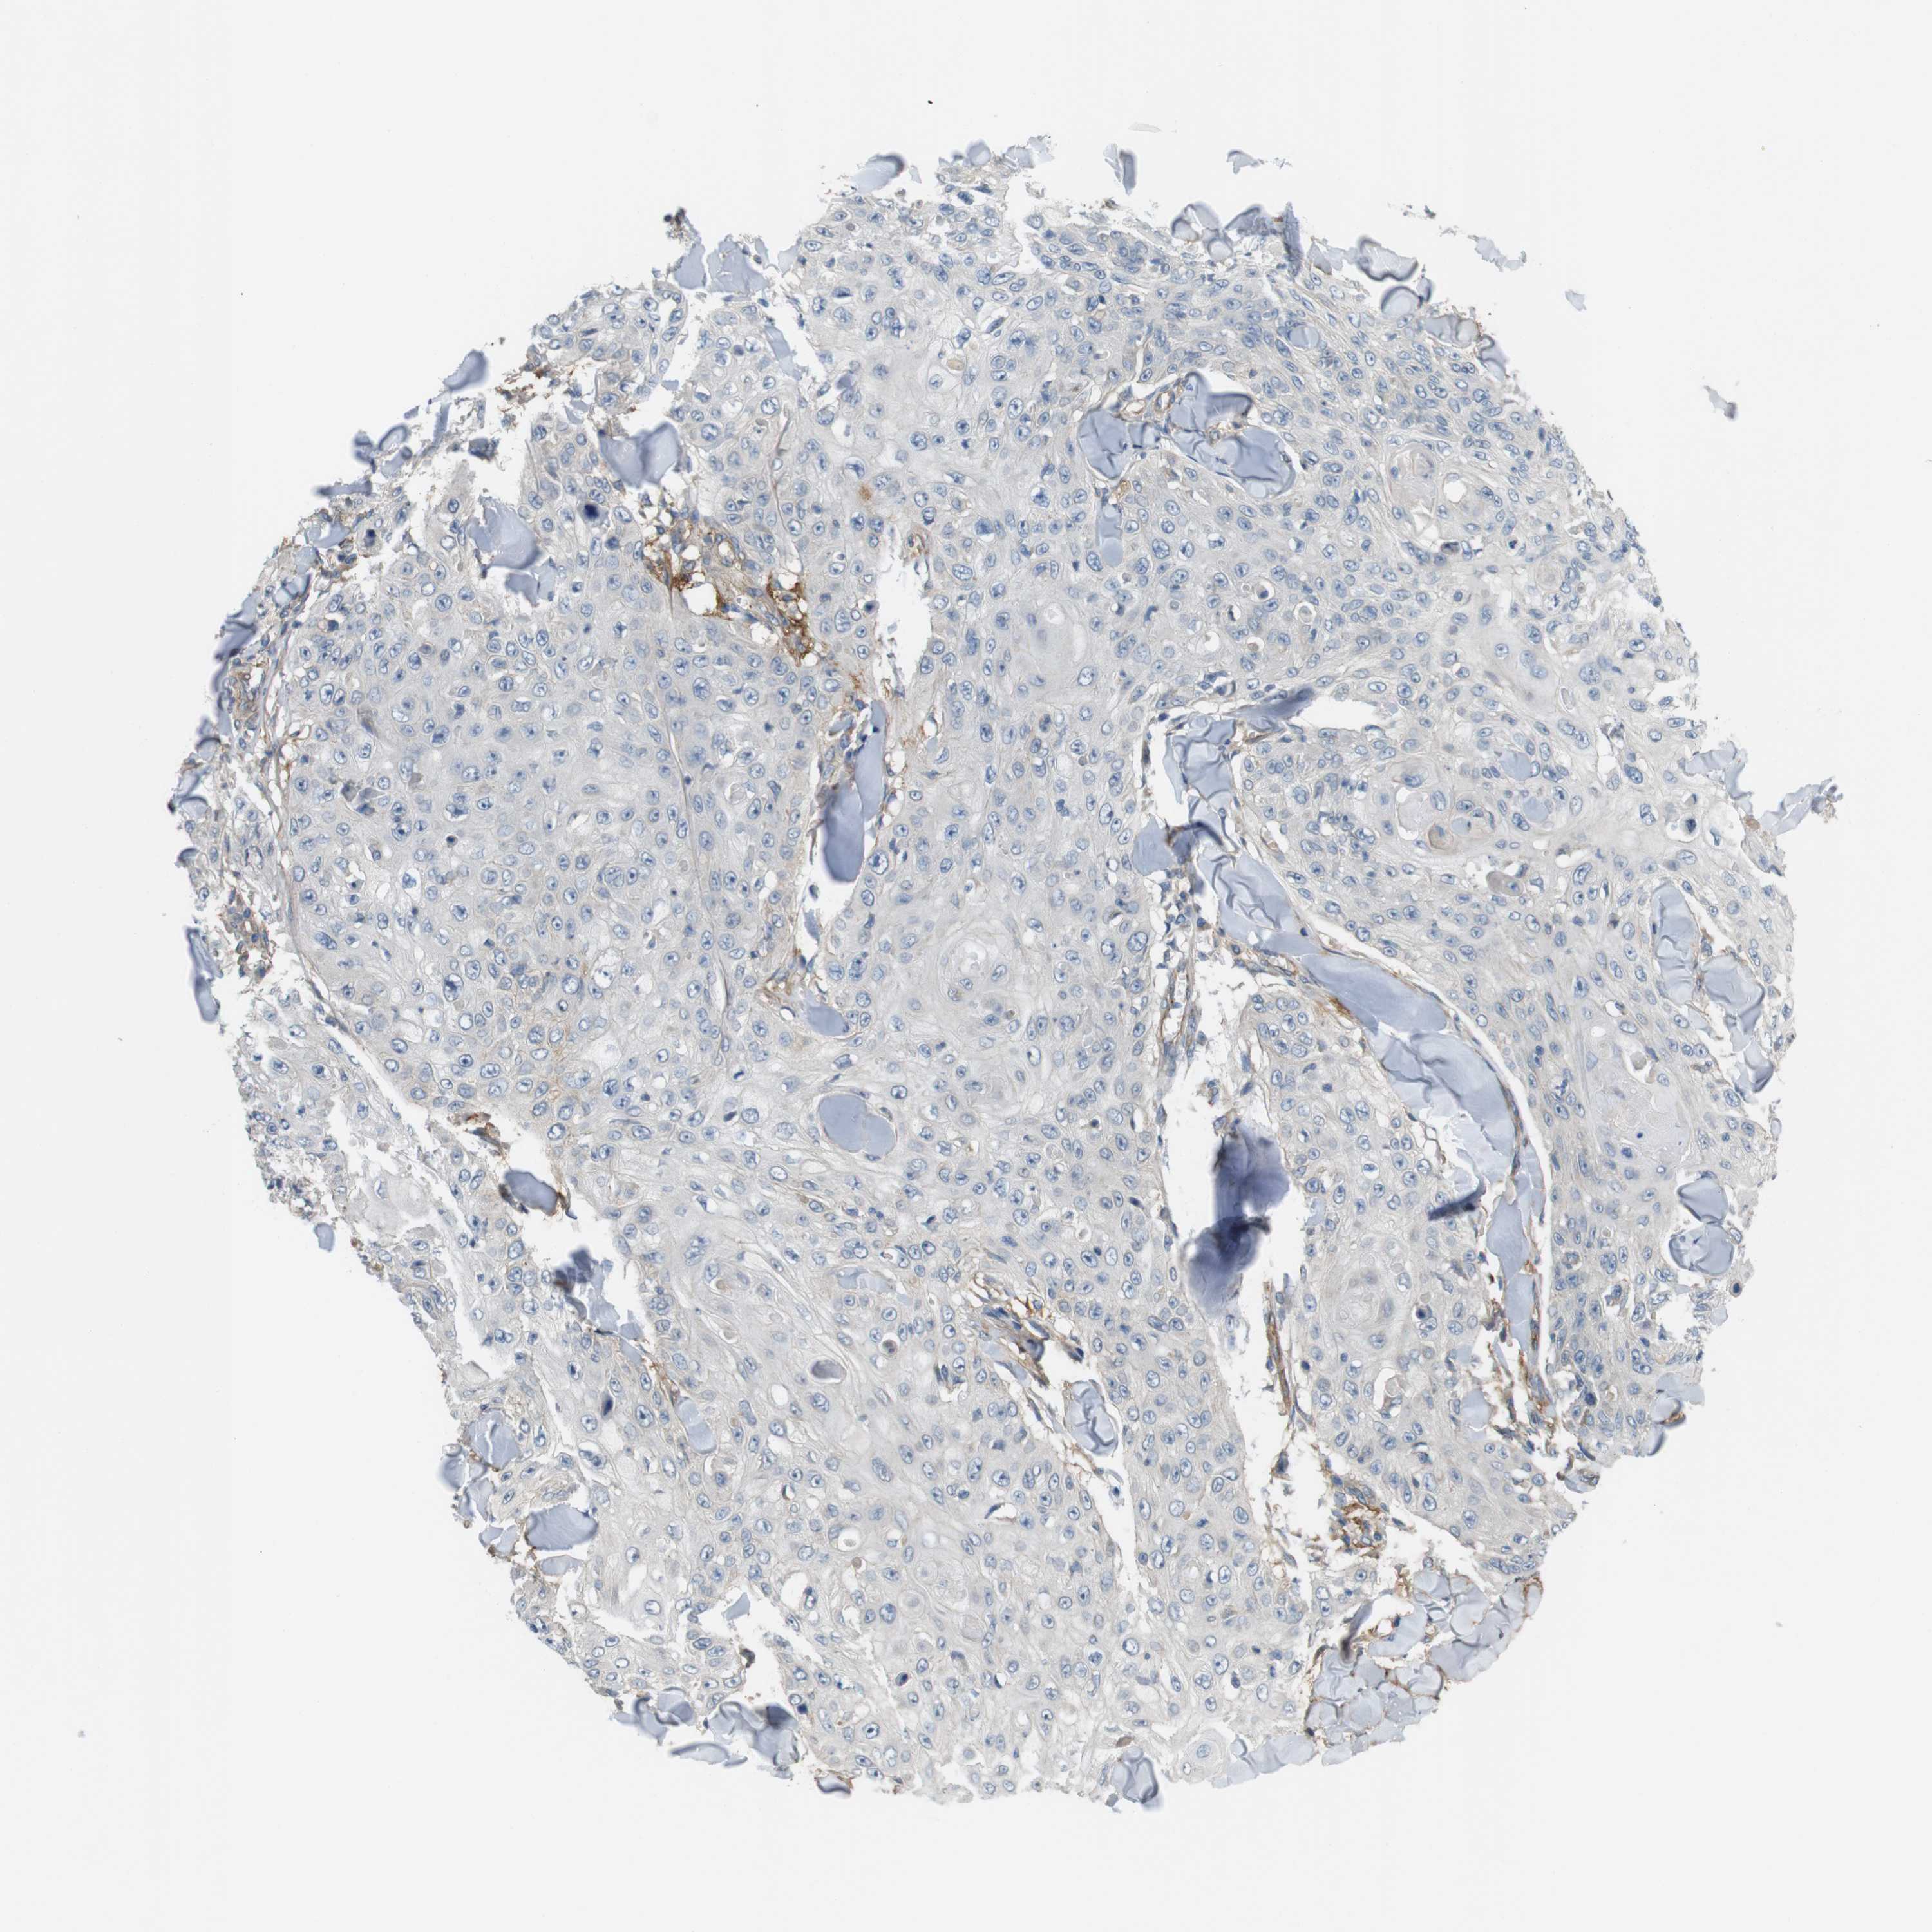

SKIN CANCER - Protein expressioni

A mouse-over function shows sample information and annotation data. Click on an image to view it in a full screen mode. Samples can be filtered based on level of antibody staining by selecting one or several of the following categories: high, medium, low and not detected. The assay and annotation is described here.

Antibody stainingi

Antibody staining in the annotated cell types in the current human tissue is reported as not detected, low, medium, or high, based on conventional immunohistochemistry profiling in selected tissues. This score is based on the combination of the staining intensity and fraction of stained cells.

Each image is clickable and will lead to virtual microscopy that enables deeper exploration of all samples and also displays staining intensity scores, fraction scores and subcellular localization as well as patient and tissue information for each sample.

Antibody HPA018176

Squamous cell carcinoma in situ, NOS

Squamous cell carcinoma, NOS

Basal cell carcinoma

Adnexal tumor, benign

Squamous cell carcinoma, metastatic, NOS